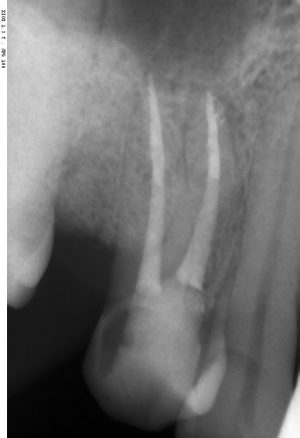

После операции:

— контрольный снимок (раньше делали ОПТГ, сейчас — строго КЛКТ)

Серия контрольных снимков на этапах:

Вот так закончилась 12-летняя эпопея Зинаиды с восстановлением зубов на нижней челюсти. Через пару дней она уехала на экскурсию в Санкт-Петербург (на всякий случай, мы попросили задержаться в России, вдруг потребуется коррекция), а оттуда — домой, в дружественную страну. Судя по тому, что она нам пишет — у неё всё прекрасно и хорошо. Зинаида обещает не пропускать профилактические осмотры и наблюдаться у стоматолога по месту жительства.